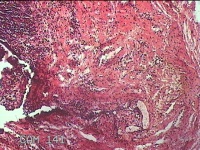

右侧外阴囊肿囊壁

性别

女

年龄

35岁

临床诊断

右侧前庭大腺囊肿

一般病史

发现右侧外阴囊肿1年。

标本名称

大体所见

白暗红色囊性肿物2.3x1.5x0.8cm一个,表面光滑,部分已切开,囊内容物已流失,囊壁厚0.1cm。

良性病变。